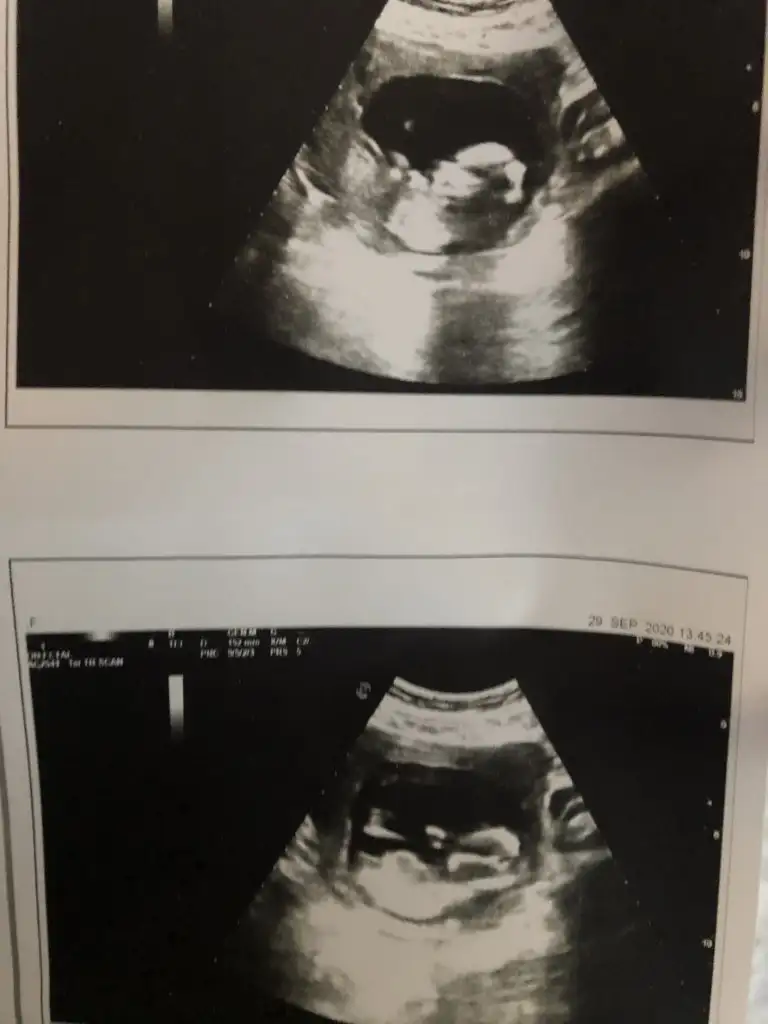

ErkekMerhaba 10+6 günlük ama bir türlü düzgün yakalayamadı doktor çok hareketliydi. Tekrar 13. Haftada gitmis olacağım var mı bir tahminin acabaIkra meyra

Kız gibi ama en iyi 11 12 13 haftalar olmalı